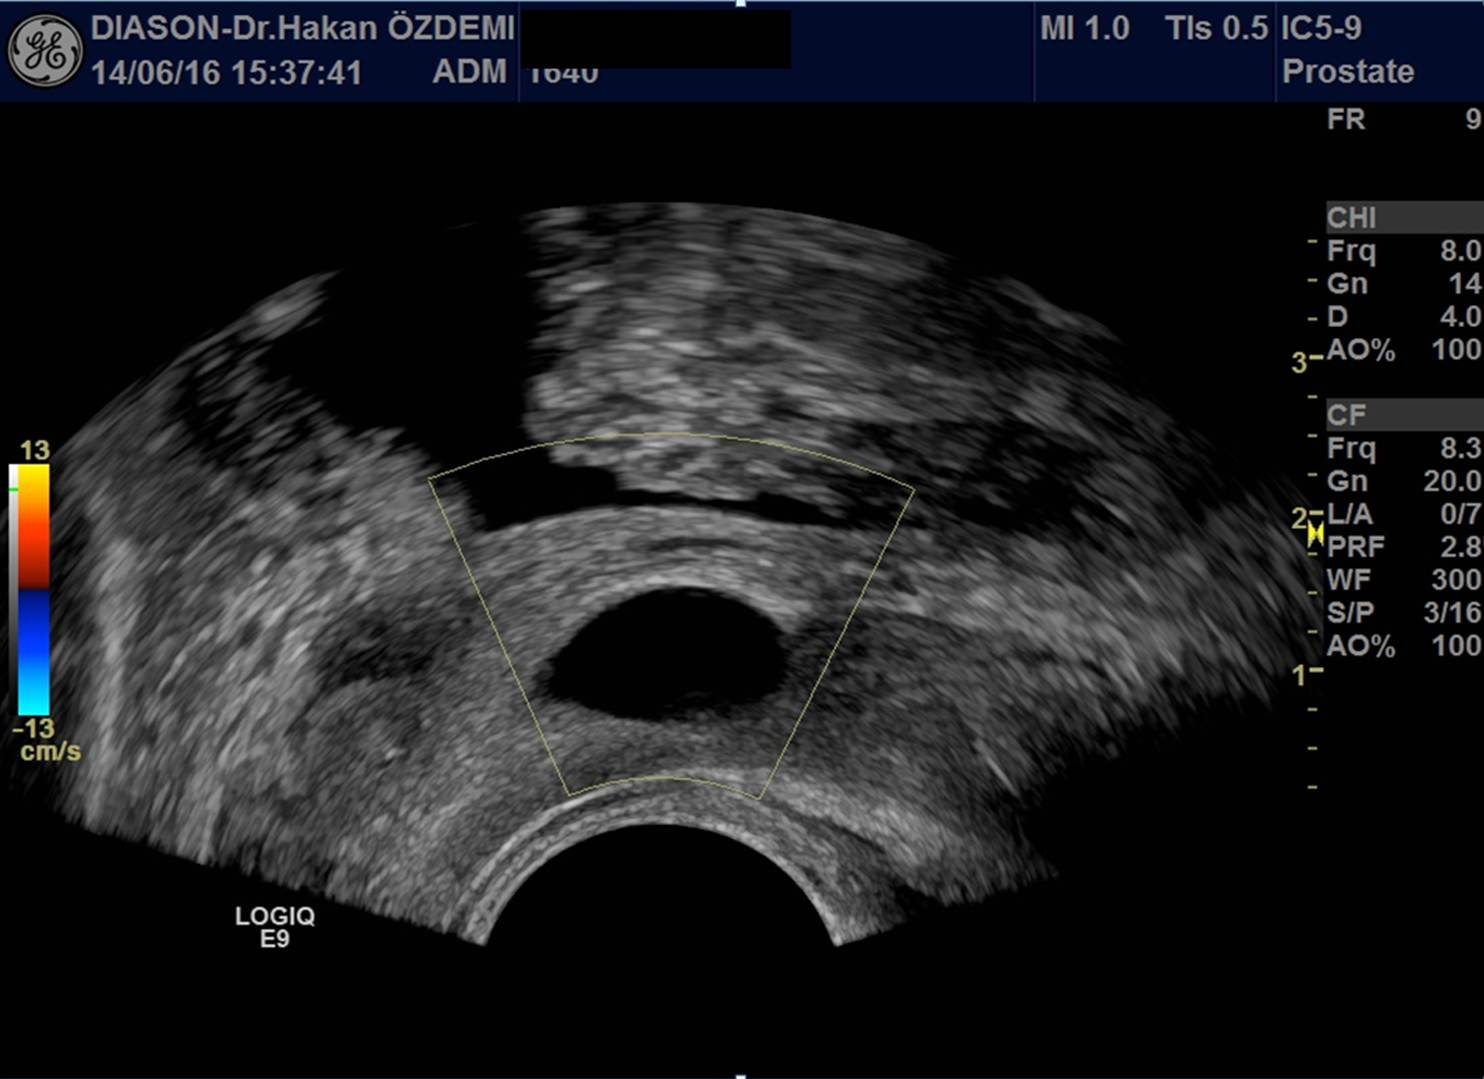

Ultrason, yüksek frekanslı ses dalgaları (ultrases) kullanılarak vücut içindeki organların ve diğer yapıların görüntülenmesi yöntemidir. Ultrasonda kullanılan ses dalgaları insan kulağının işitemeyeceği kadar yüksek frekansa sahiptir. Ultrason görüntülemede iyonizan radyasyon (X-ışınları) kullanılmadığı için bilinen zararlı etkisi bulunmamaktadır.

Ultrason cihazı, içerisinde bilgisayar ve elektronik aletlerin bulunduğu bir konsol, görüntülerin izlendiği bir ekran ve vücudu taramada kullanılan prob (transdüser) dan oluşmaktadır.

İnceleme sırasında prob ile vücut yüzeyi arasındaki temas jel aracılığı ile sağlanmaktadır. İncelenen bölgeye jel sürülmesinin nedenleri yüzeyin kayganlaştırılmasını sağlamak ve probun hava ile temasını önlemektir. Ultrason görüntülemenin temeli, yarasalar ve gemilerin kullandığı "sonar" ile aynıdır. Ses dalgaları vücuttan geçerken oluşan yansımalar, objenin uzaklığı, büyüklüğü, şekli ve yoğunluğunu tanımlamada kullanılır.

Ultrason probları, hem ses üreteci (hoparlör) hem de ses alıcısı (mikrofon) olarak çalışır. Prob cilde bastırıldığında vücut içine yüksek frekanslı, duyulamayan ses dalgaları yollar. Ses dalgaları vücuttaki doku ve sıvılardan yansıdıkça, prob yansıyan dalgaların özelliğini ve şiddetini kaydeder. Doppler ultrason da ise, prob ses dalgalarının yönü ve şiddetindeki küçük değişiklikleri kaydeder.

Bu yansımalar prob içinde bulunan özel kristaller aracılığıyla elektrik sinyallerine dönüştürülür. Daha sonra cihazın içinde yeralan bilgisayar aracılığı ile bu sinyallerden ekranda izlenen gerçek zamanlı görüntüler oluşturulur.